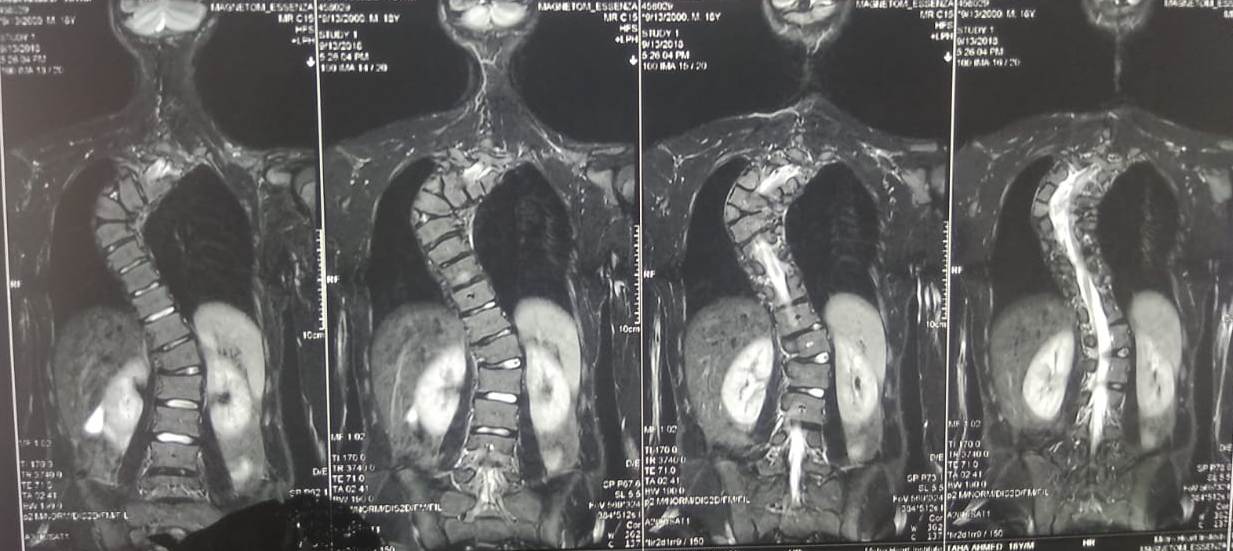

MRI Before Surgery